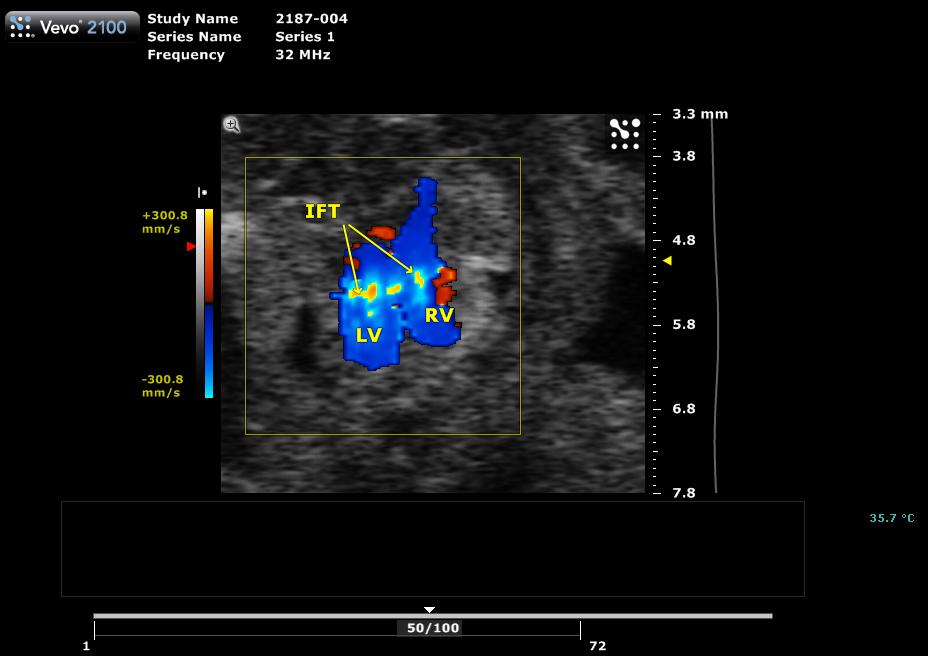

Caption Color flow spectral Doppler imaging of mutant fetus 2187-004-1 (E16.5) in the transverse view shows aliasing with increased blood flow through inflow tracts, suggesting atrioventricular valve stenosis